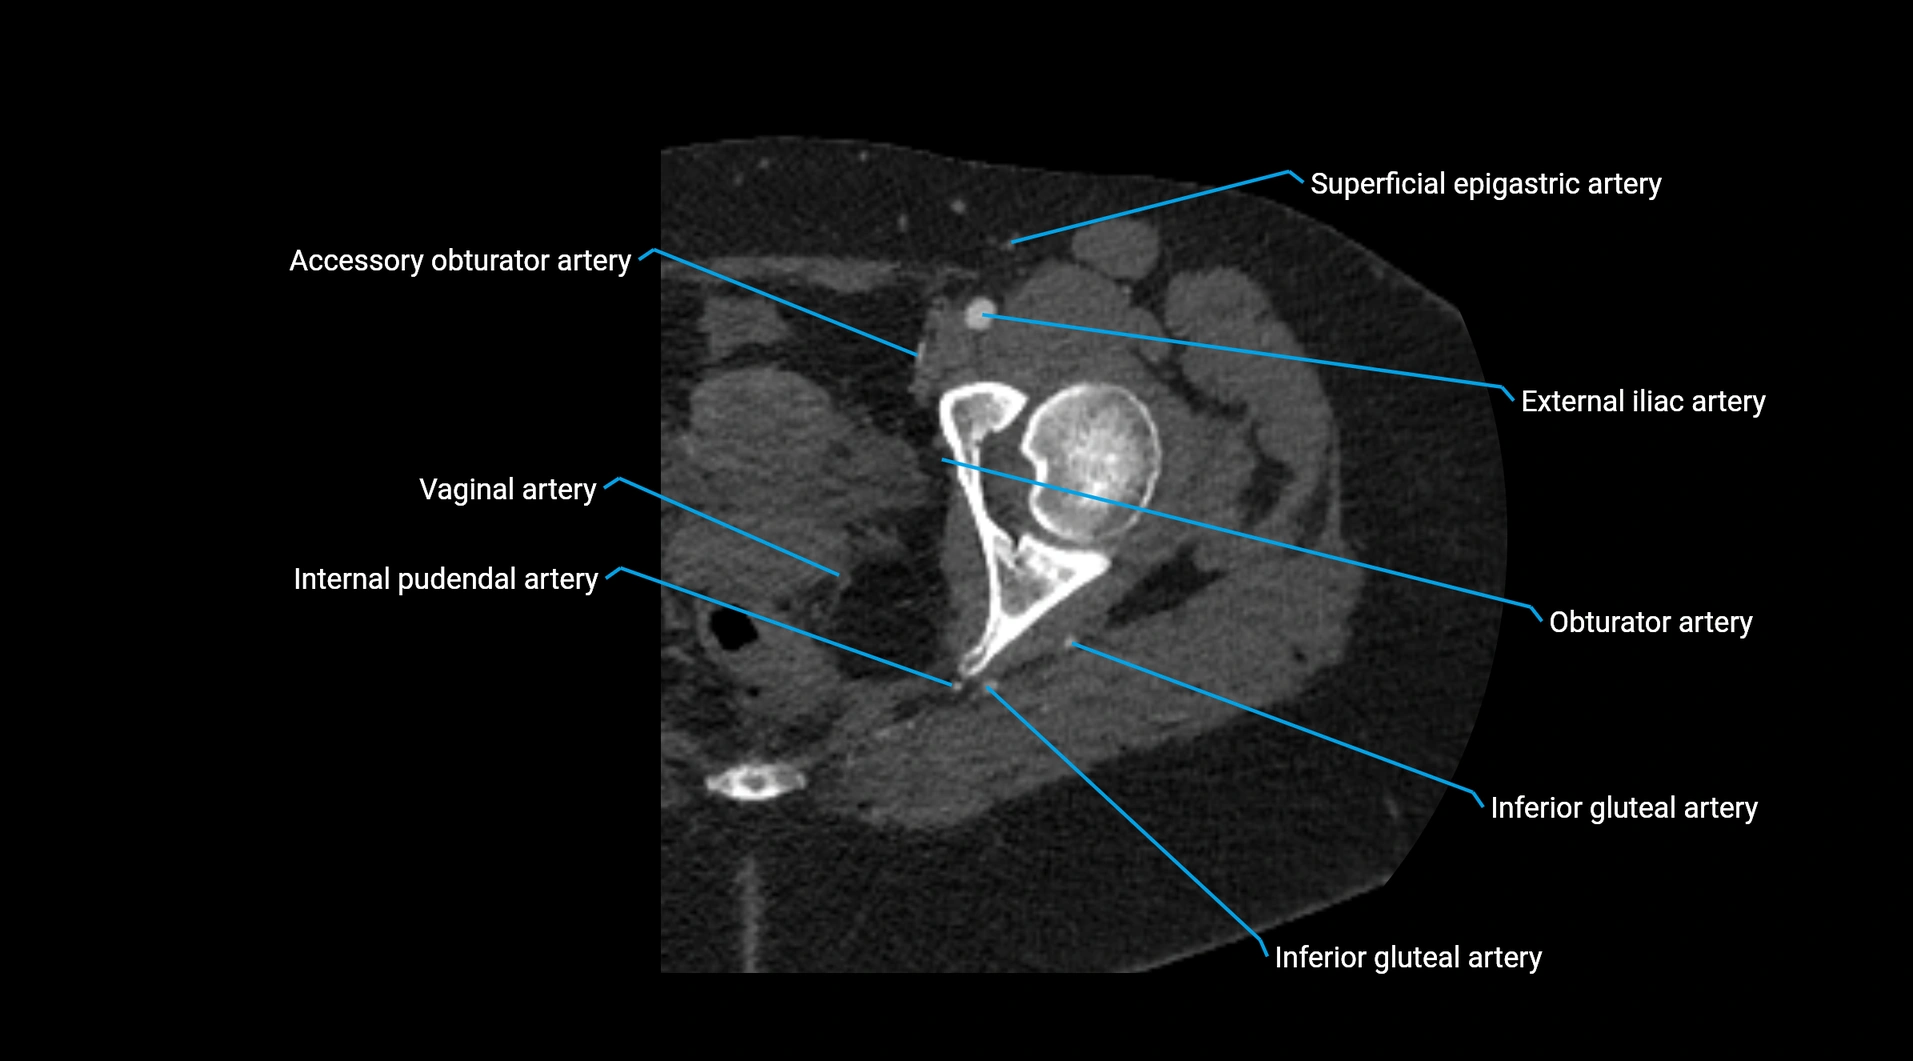

CT images

image

Contrast-enhanced CT (CTA):

• Gold standard for abdominal aortic imaging

• Provides excellent detail of lumen, wall, aneurysm, thrombus, and branch vessels

• Multiplanar and 3D reconstructions help in aneurysm measurement, stent graft planning, and dissection evaluation

• Paired visceral branches: middle suprarenal arteries, renal arteries, gonadal arteries (testicular or ovarian)

• Parietal branches: inferior phrenic arteries, lumbar arteries, median sacral artery